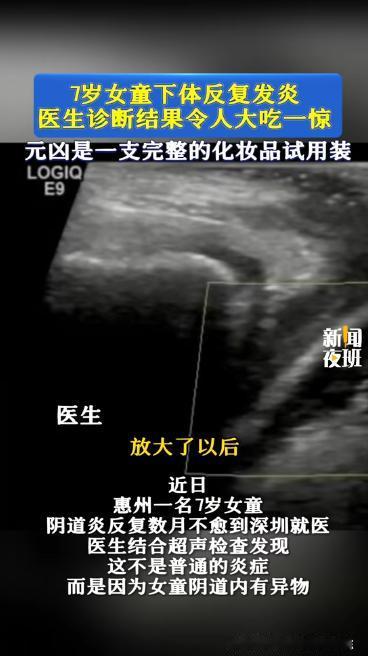

“万万没想到!”近日,广东,一7岁女孩阴道炎反反复复,家长试过什么办法都不见好,

2026-04-10

云舟史策说

标签:

阴道炎

医生

儿童健康